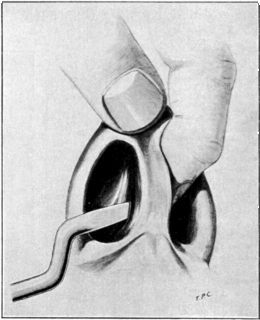

| 42. | Simon’s Operation for the Repair of a Vesico-vaginal Fistula | 136 |

| 43. | Repair of a Vesico-vaginal Fistula by Dédoublement | 137 |

| 44. | Repair of a Vesico-vaginal Fistula. Sims’s Operation | 137 |